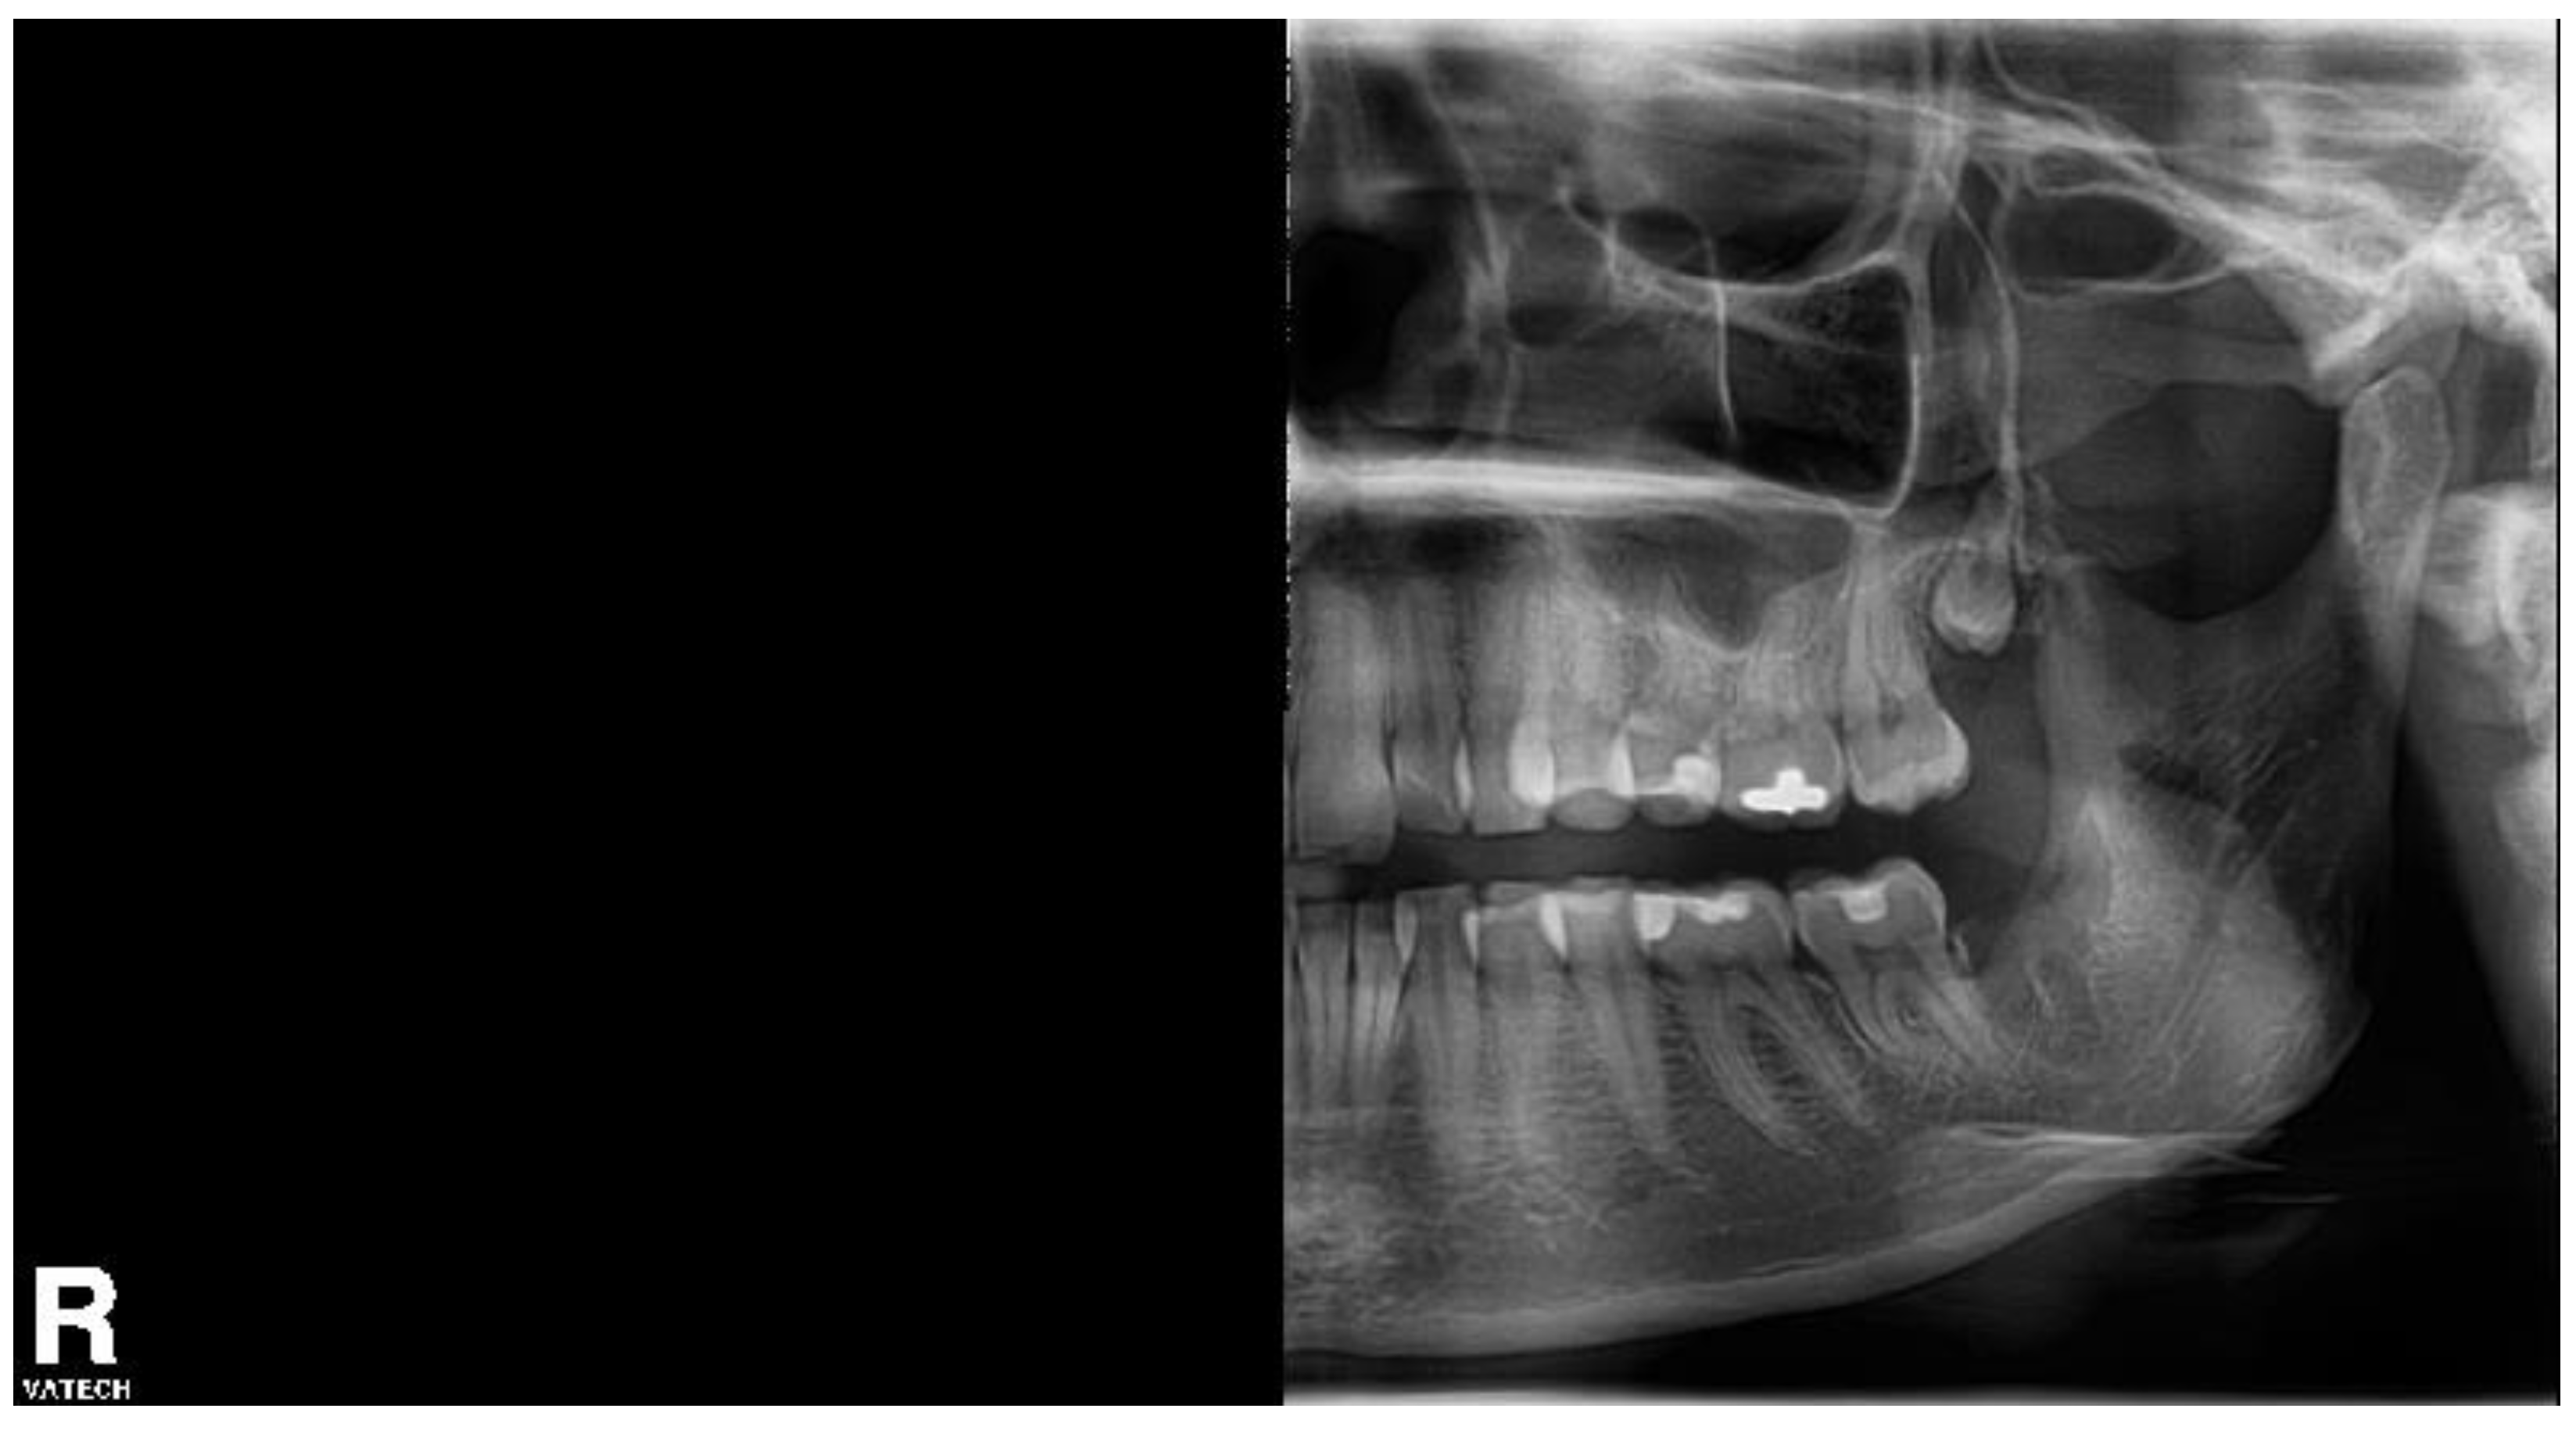

A 28-year-old female patient underwent a transalveolar extraction of the tooth No. 38 at another workplace for repeated pain in that area. The patient used antidepressive drugs, declared no allergies, and smoked 10 cigarettes a day. The extraction lasted for 45 min, according to the patient.

The pain started immediately after extraction, the patient used painkillers (the drug name was not specified) with no significant effect, and four days later, she came to our department. She complained of pain in the extraction wound, VAS 38/100. There was no extraoral swelling, the range of mouth opening was limited to 2.5 cm, the extraction wound was filled with detritus, and the surrounding mucosa was painful upon palpation. A half OPG was taken to confirm no broken root in the socket (Figure 6). Without local anesthesia, the wound was rinsed with 3% hydrogen peroxide, water for injection, and the HA + OCT device was inserted.

Figure 6. The half orthopantomogram of the left side of the patient 5. An empty socket of the tooth No. 38 is visible.